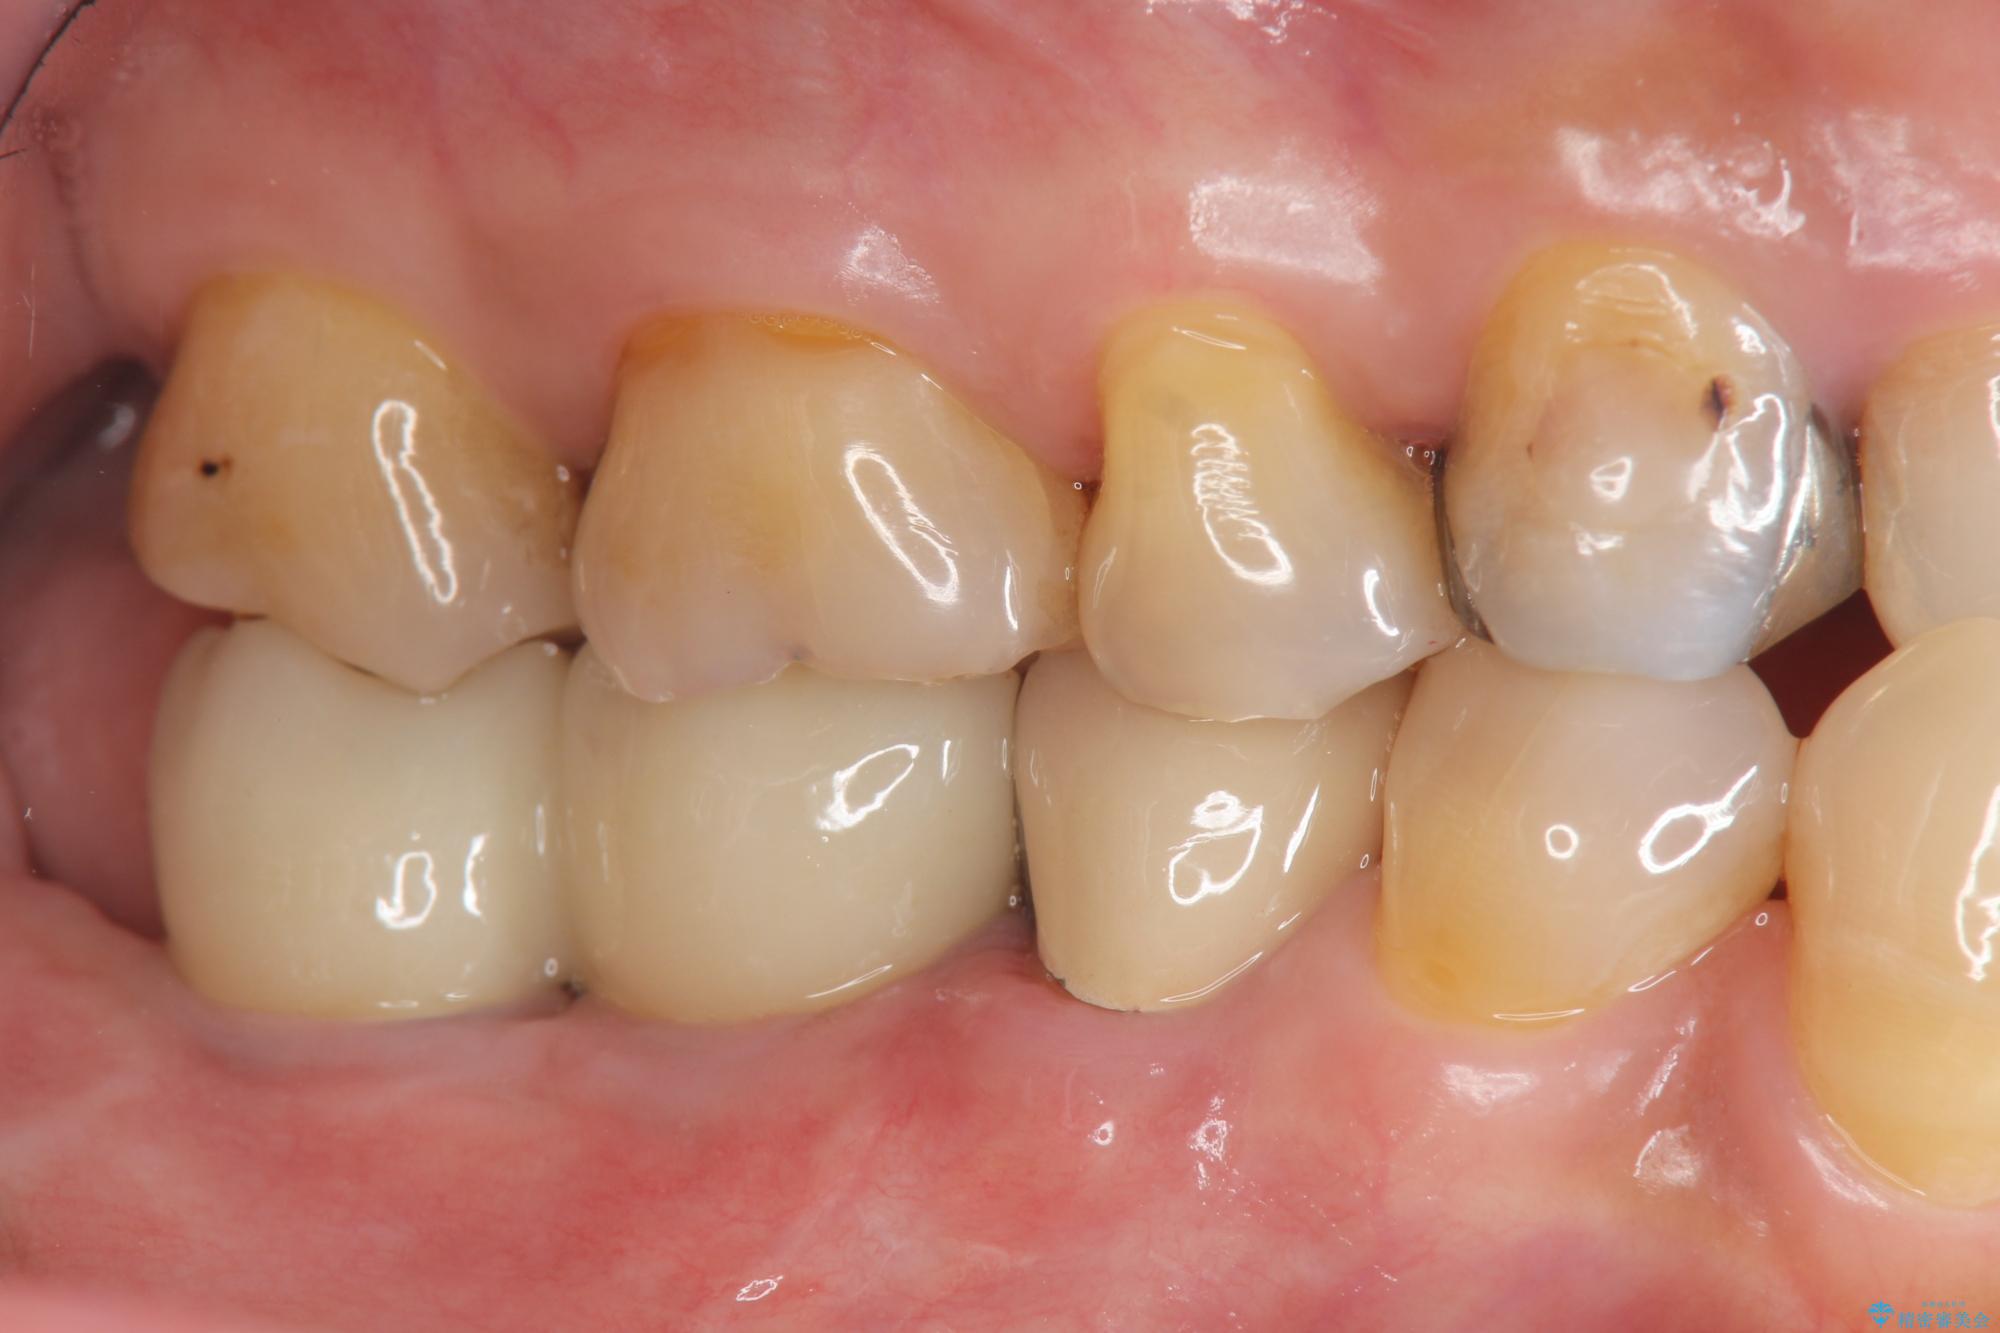

治療前

奥歯から膿のにおいがする インプラントによる機能回復 治療前画像 奥歯から膿のにおいがする インプラントによる機能回復 治療前画像 奥歯から膿のにおいがする インプラントによる機能回復 治療前画像 奥歯から膿のにおいがする インプラントによる機能回復 治療前画像 奥歯から膿のにおいがする インプラントによる機能回復 治療前画像 奥歯から膿のにおいがする インプラントによる機能回復 治療前画像